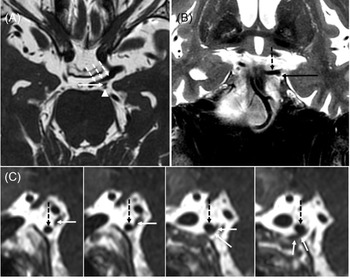

A diagnosis of partial pupil-sparing left TNP was suspected and an MRI and MR angiography of the brain and orbits with contrast was performed. It revealed bilateral, left more greater than right, dolichoectatic PCommA with the left PCommA abutting and displacing the third nerve (Figure 1). There was no aneurysmal dilatation of the affected vessel wall.

Figure 1: Large left posterior communicating (PComm) artery displacing the left oculomotor nerve. (A) Axial 3D FIESTA sequence shows a large left PComm artery (dashed arrows), the left oculomotor nerve (arrow), and the left superior cerebellar artery (arrowhead). (B) Coronal T2-weighted image shows the left oculomotor nerve (arrow) coursing along the undersurface of the left PComm artery (dotted arrow). (C) Series of sagittal reformats from the 3D FIESTA sequence shows the left PComm artery (dotted arrows) indenting the left oculomotor nerve (arrows).